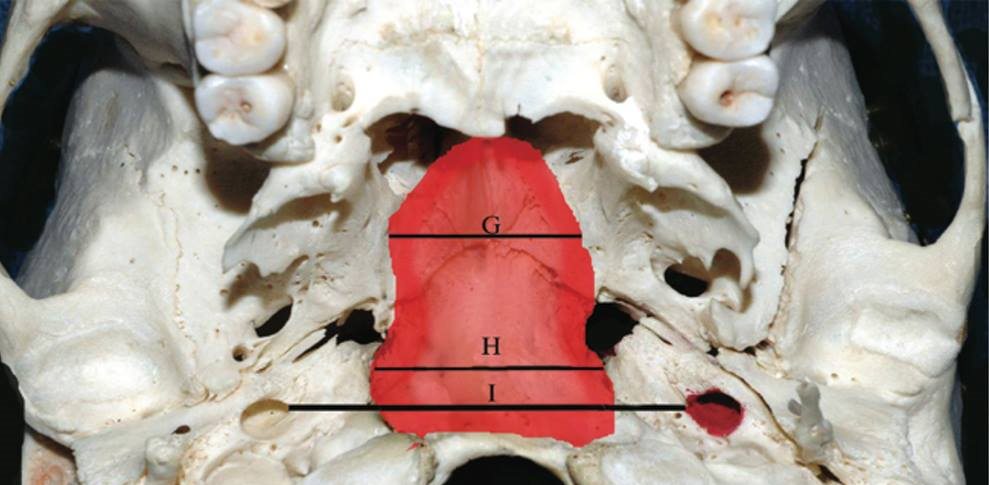

Lesões clivais medianas

Lesões clivais medianas, sejam envolvendo o clivus ou simplesmente situadas anterior ao tronco cerebral, apresentam um desafio técnico para uma exposição adequada e uma ressecção segura. Através de técnica minimamente invasiva, a clivectomy anterior, realiza-se uma abordagem transesfenoidal expandida, juntamente com a utilização de neuronavegação na cabeça móvel e de técnica endoscópica assistida.